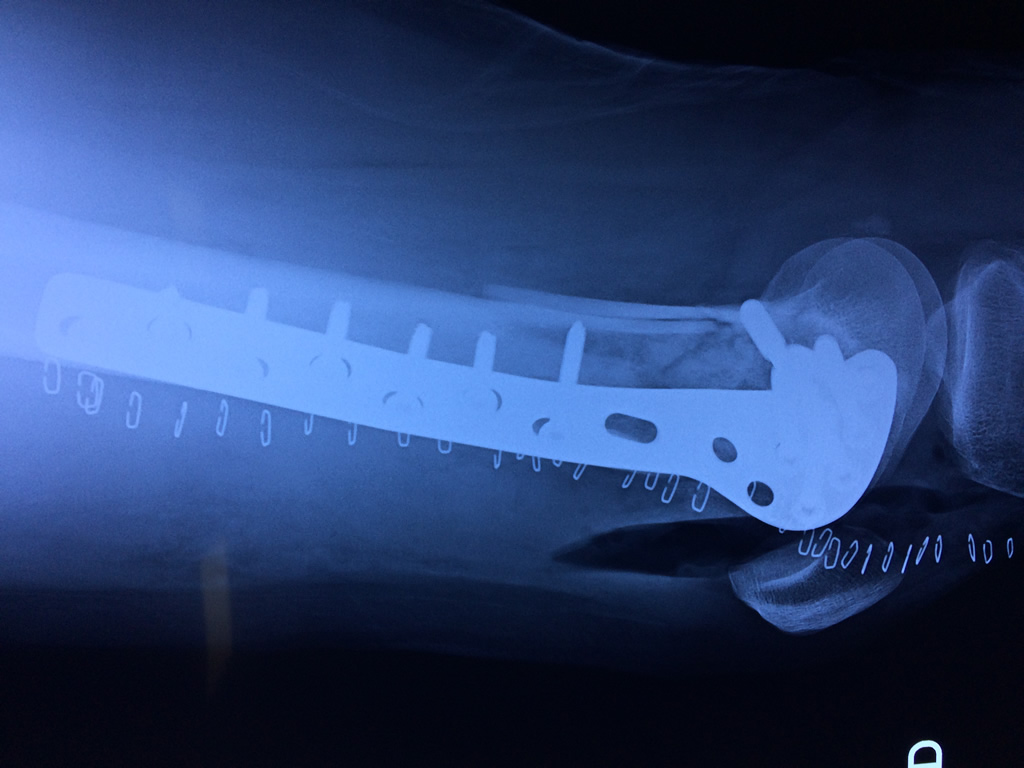

Fémur - Fémur

El fémur es el hueso del muslo, el segundo segmento del miembro inferior. Es el hueso más largo, fuerte y voluminoso del cuerpo humano.